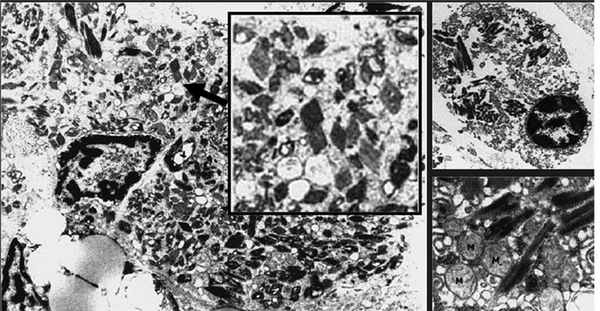

Возможны и другие формы ассоциированной с MGUS тубулопатии. Хорошо известно, что ЛЦ способны подвергаться реабсорбции и кристаллизации в цитоплазме канальцевого эпителия с развитием различных дисфункций канальцев — парциальных или по типу синдрома Фанкони. Кристаллизация Л.Ц. является фактором трансформации канальцевого эпителия в клетки макрофагального ряда с развитием гистиоцитоза (рис. 1). Однако следует отметить, что такая кристаллизация происходит во многих тканях и связана с тем, что лизосомальный аппарат резидуальных макрофагов оказывается неспособным полностью лизировать ЛЦ. У пациентов в этом случае нередко развивается генерализованный гистиоцитоз. Способность канальцевого эпителия почек трансдифференцироваться в клетки макрофагального ряда хорошо известна, это свойство является важным механизмом фиброза в почках у больных с протеинурией. Способность к трансдифференциации, по-видимому, связана с единством происхождения канальцевого эпителия и макрофагов из одного и того же эмбрионального листка — мезодермы.

Рис. 1. Гистиоцитоз с внутриклеточными кристаллами (A. Lebeau, E. Zeindl-Eberhart, 2002).